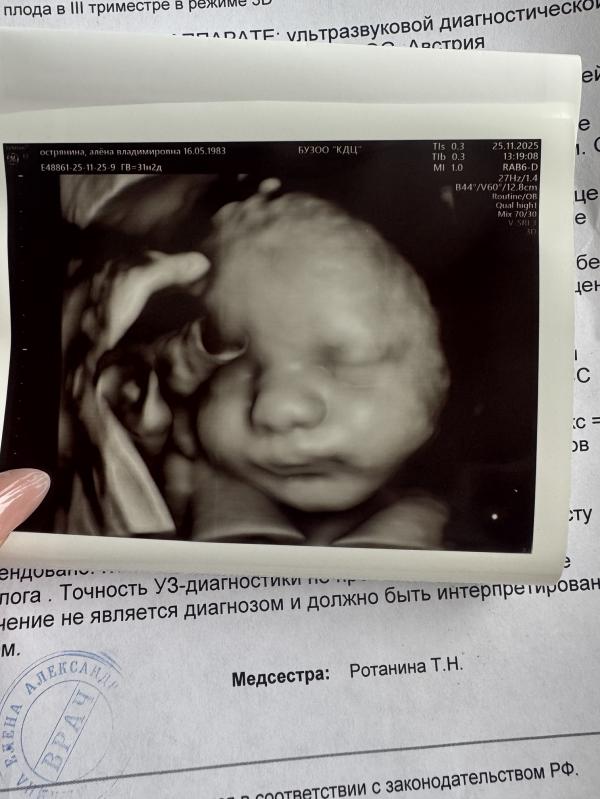

Еще один этап пройден!!! Ура-а-а! Третий скрининг пережили. С малышом все хорошо. Но... Как всегда, без сомнений не обходится. Вес 2318, малыш на срок 34 недели, а это на две недели больше того срока, что выставлен. Плацента степень зрелости 2. Девочки, что это все в совокупности может значить? Готовится к родам раньше времени? Есть вероятность родоразрешения раньше времени? Т хорошо же все, но вопросы в голове не дают покоя.

Ну а щёчки конечно мы наели хорошенькие. Хомячок растёт